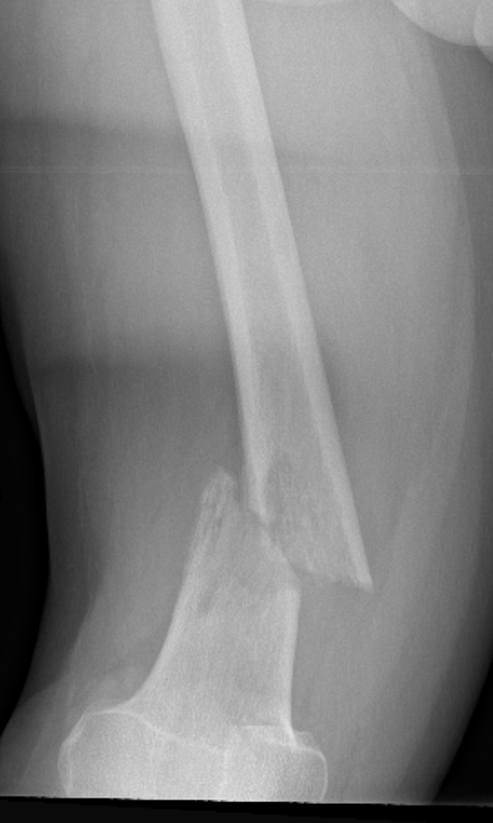

Humeral shaft

Options

Plate +/- cement

IMN +/- cement

Results IMN

Moura et al Rev Bras Ortop 2019

- 86 pathological humeral fractures treated with IMN

- 5% surgical complication rate

- 100 IMN for pathological humerus fracture

- surgical complication rate 11% with cement, 4% without

Results plate

- 63 pathological humerus fractures

- all treated with cement + plate

- 11% reoperation rate

IMN versus plate

- stabilization of humerus pathological fracture

- broken implant 0% IMN at final follow up

- broken implant 14% plate + cement at final follow up